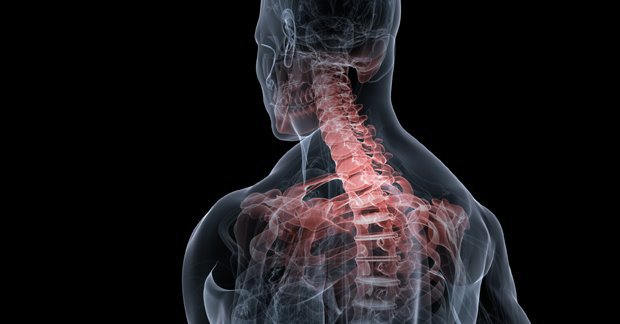

목디스크란 목뼈 사이에 있는 디스크가 손상되어 신경을 압박하는 질환을 의미합니다. 디스크는 젤리와 같은 수핵과 섬유륜으로 구성되어 있습니다. 섬유륜이 손상되면 수핵이 밖으로 밀려나와 신경을 압박하게 됩니다.

목디스크는 주로 잘못된 자세, 과도한 스트레스, 외상 등으로 발생합니다. 잘못된 자세로 장시간 컴퓨터를 사용하거나 운전을 하면 목에 무리가 가고 디스크가 손상될 수 있습니다.

또한 과도한 스트레스는 근육을 긴장시켜 디스크에 손상을 줄 수 있습니다. 외상은 교통사고, 운동 중 충격 등으로 목뼈가 부러지거나 골절되면 디스크가 손상될 수 있습니다.